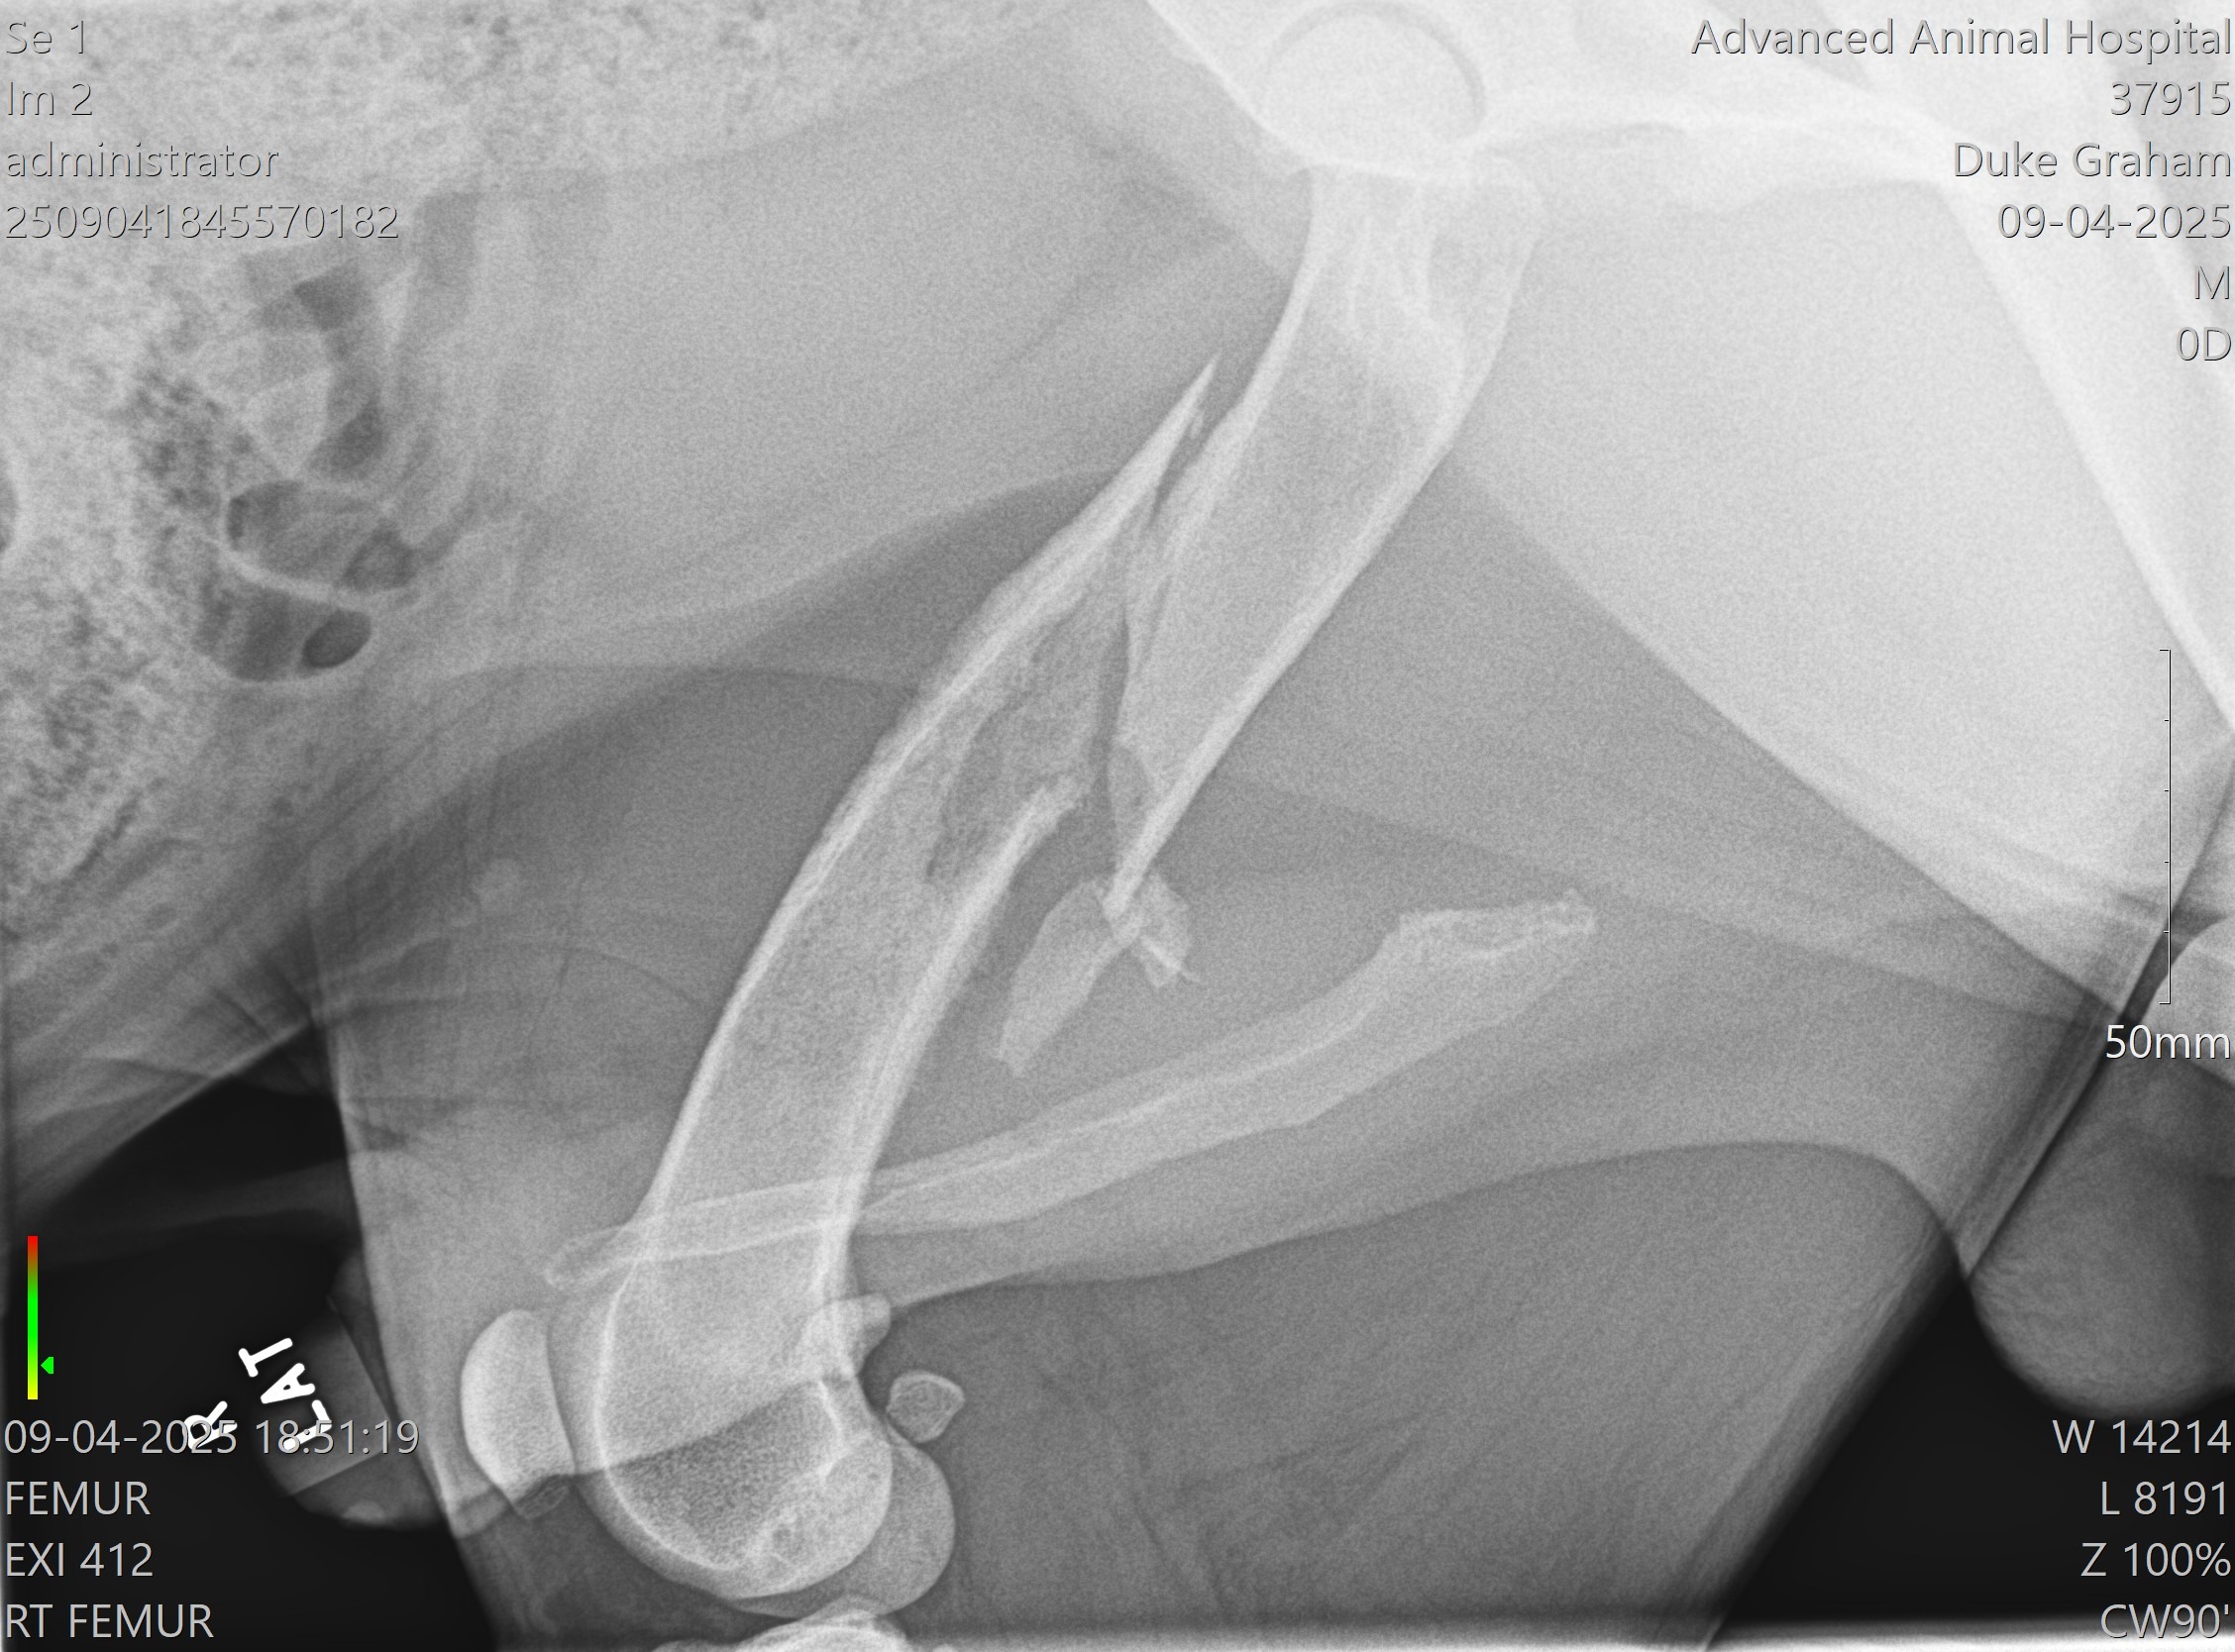

My goofy hound has found himself in a crippling situation. his femur is broken. We are currently waiting blood and other test results in order to establish the most effective way to fix his leg and/or alleviate his pain. Young and active, weighing in around 110 lbs, we are devastated...... low end (amputation) is estimated at $2500 high end (complete repair, which may or may not be an option) is estimated between $3500-$4500. I was completely not prepared for this expense in anyway. I feel horrible having to ask but ANYTHING is greatly appreciated, even prayer and well wishes.